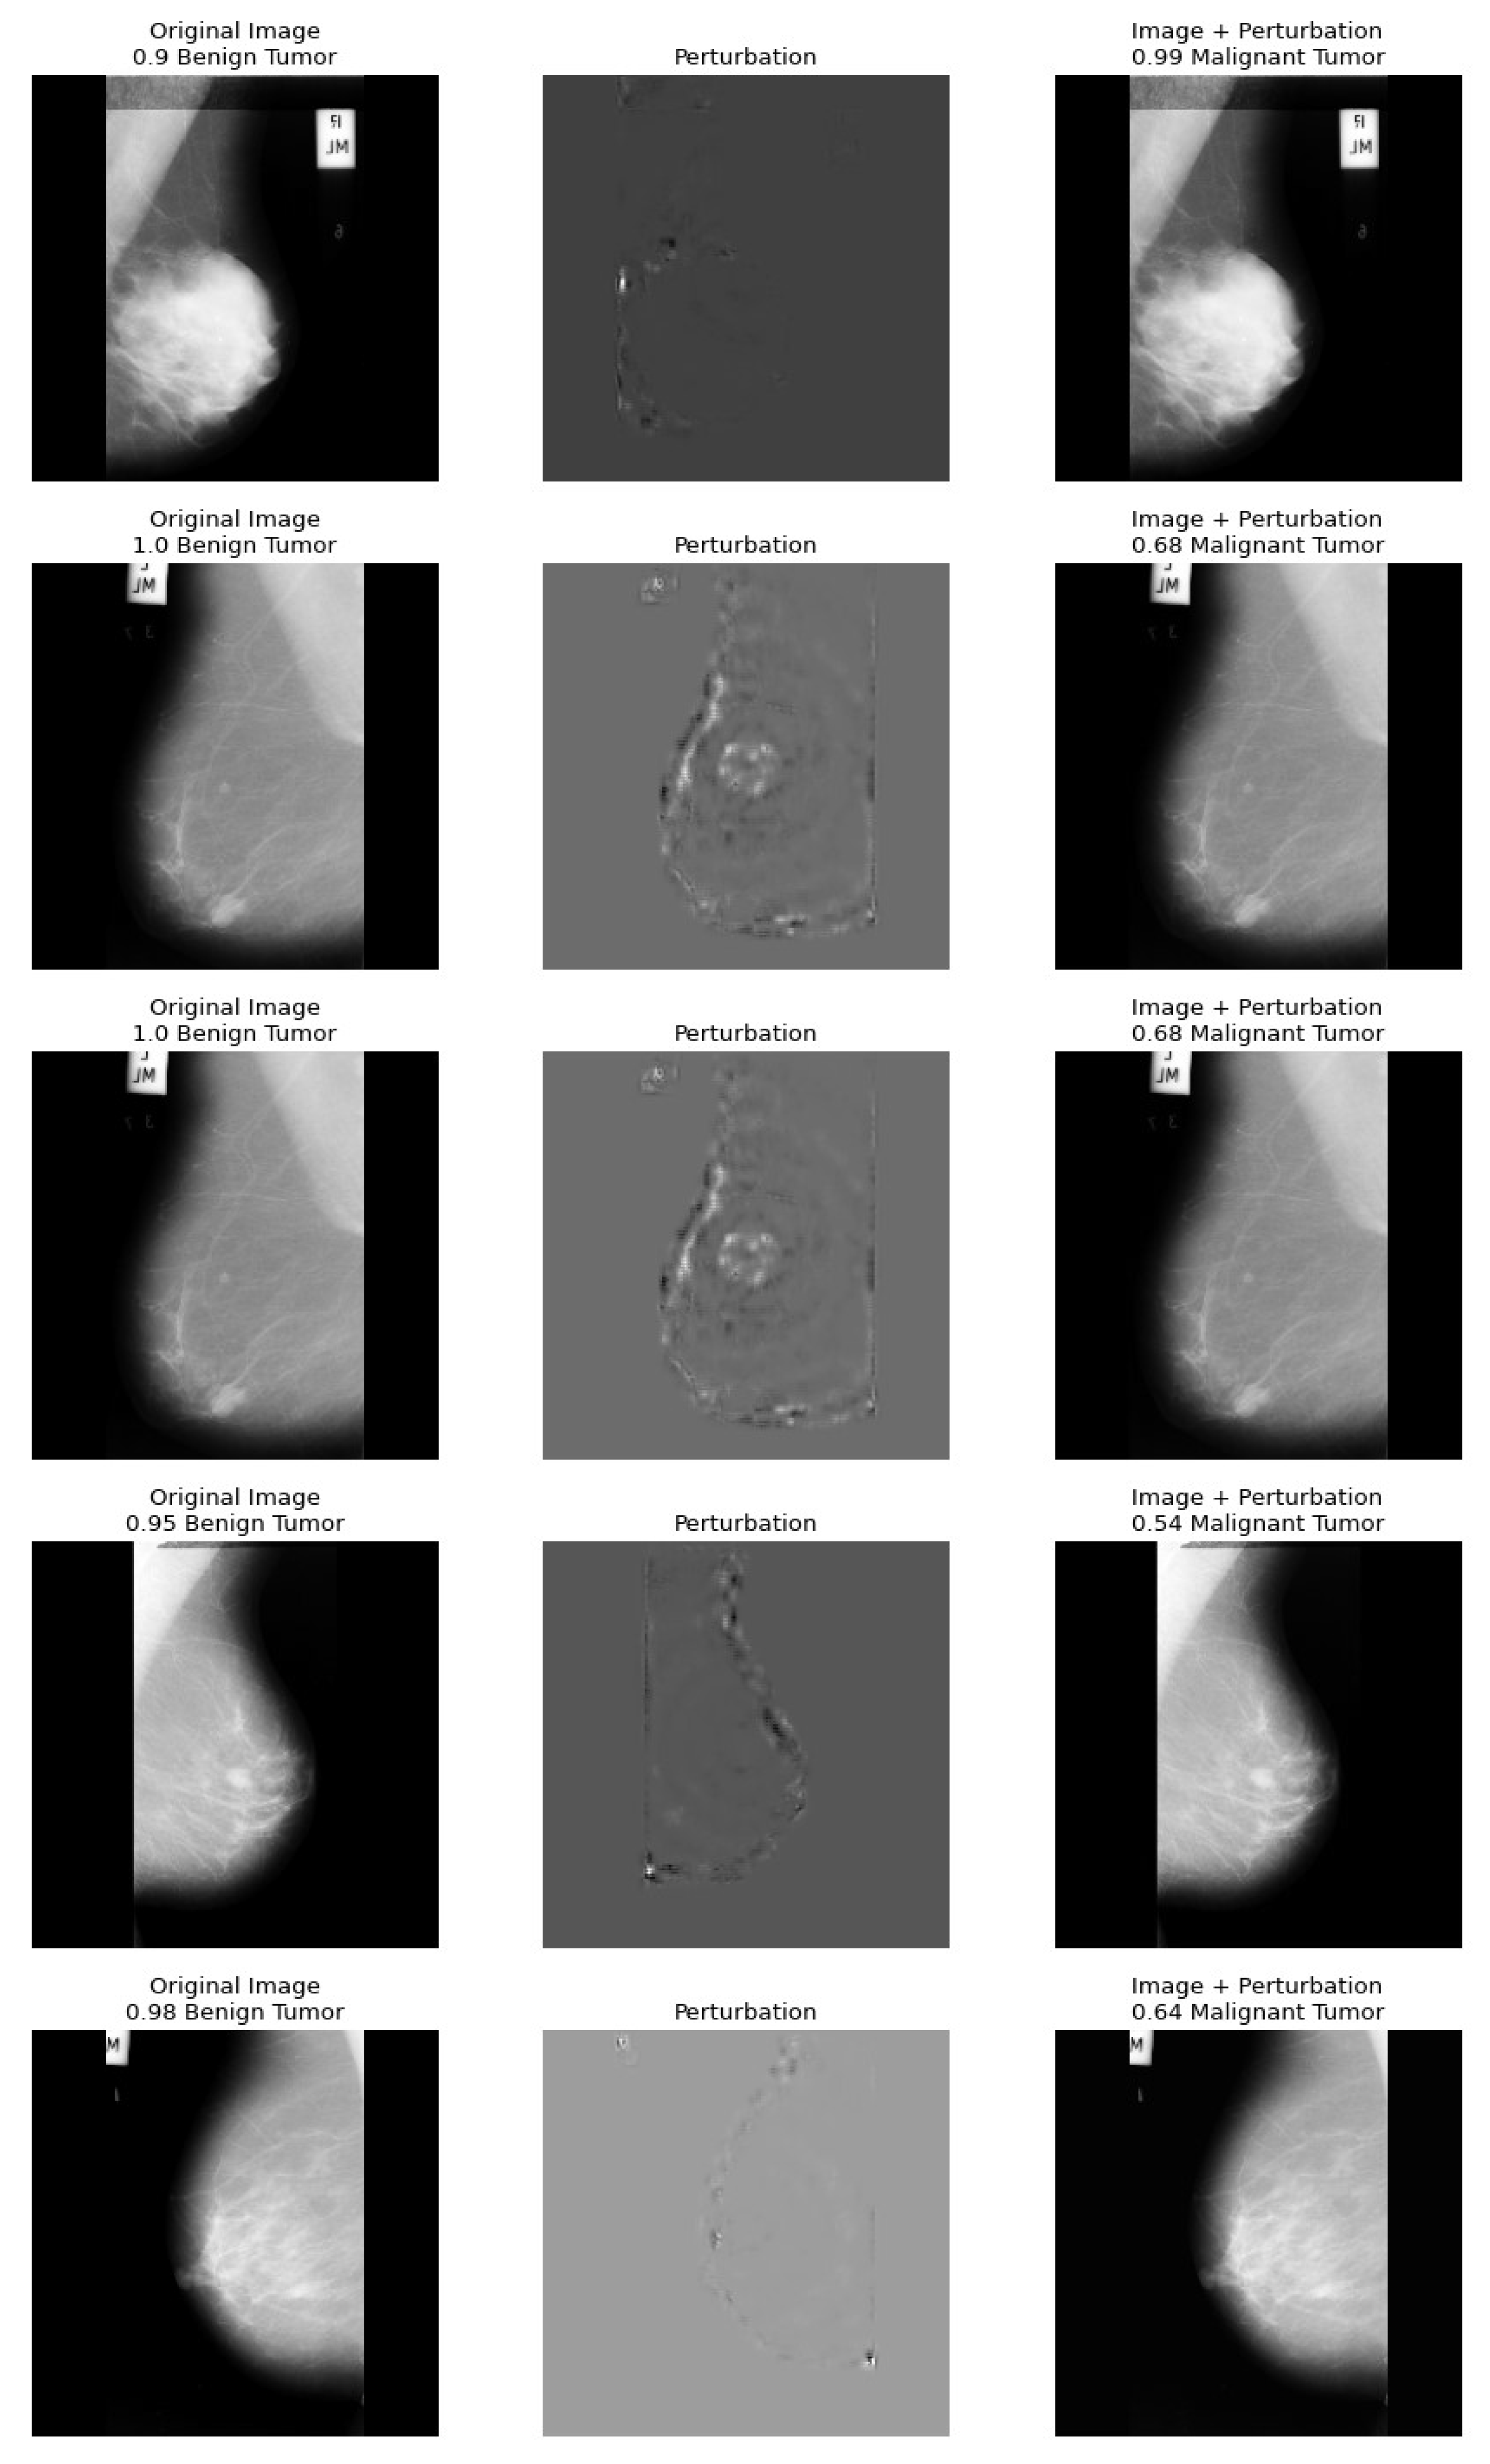

5. A Health Insurance Example and the Assessment of Damages

Dataset